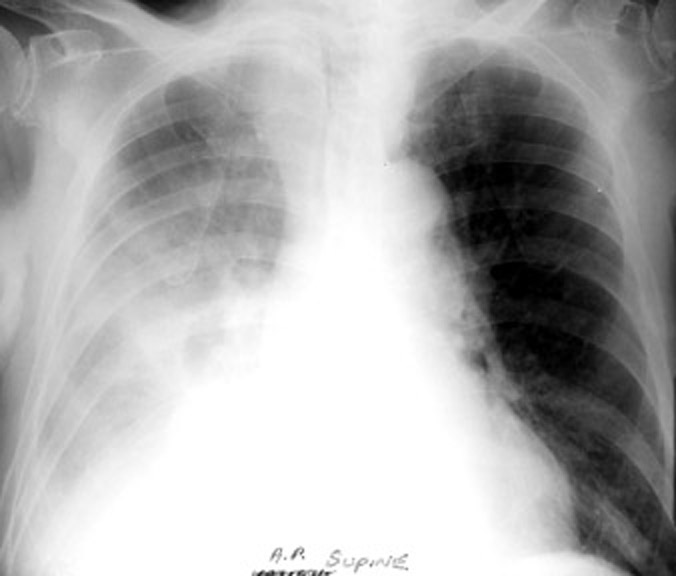

Pleural Effusion /

Upright and Supine